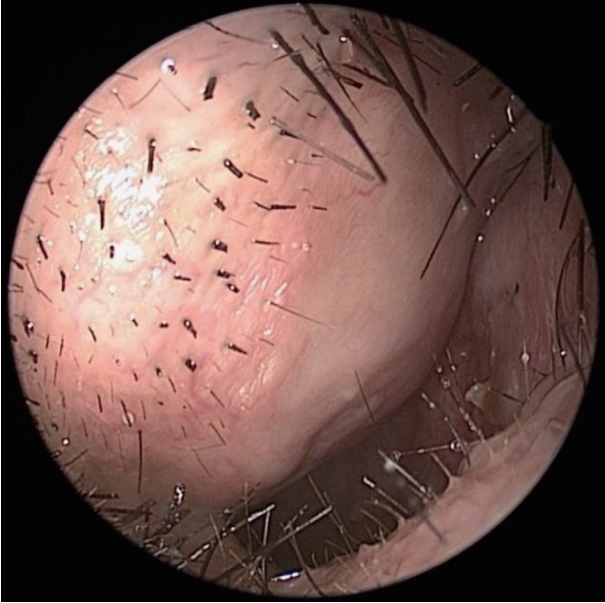

CaseA 58-year-old male patient visited our hospital with a right nasal dorsum swelling. CT scan demonstrated a 1.3×0.5 cm poorly enhanced low attenuation lesion in right nasal ala (Fig. 1). Fine-needle aspiration cytology tests confirmed benign myxoid spindle cell lesions. Surgery was recommended, but the patient refused the operation. Five years later, the patient returned to the hospital because the swelling of the right nose worsened (Fig. 2). MRI demonstrated a 1.7×1.3×1.2 cm T1-weighted image low signal intensity, T2-weighted image high signal intensity, and peripheral enhanced soft tissue lesion in right nasal ala (Fig. 3).

We performed endoscopic mass removal through the right nasal cavity. After an incision was placed in the right ala, the mass and the mucous membrane surrounding the mass were carefully peeled off and completely removed (Fig. 4). Histological examination confirmed the diagnosis of a myxoma (Fig. 5). After 9 months of surgery, patient is being followed up without complications or cosmetic problems (Fig. 6).

Radiographically, myxomas are usually well-defined ovoid masses with bony destruction or remodeling that show attenuation similar to that of water on CT [2]. On MRI, the tumor exhibits the signal intensity characteristic of fluid [6]. Intraoperatively, most masses are usually identified as glistering gelatinous masses which are oval or spherical in shape [2,4,7]. Histologic features of myxoma include spindled and stellate cells embedded in a fibromyxoid background [2,5,7,8]. Therefore, the definitive diagnosis of myxoma is made by microscopic examination to identify bland spindle cell myxoid lesion [2-6]. The spindled cells of myxoma will stain positively for vimentin and may show some positivity for S-100 protein and muscle-specific actin [2].